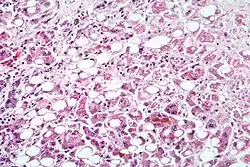

Alcoholic hepatitis as seen with a microscope, showing fatty changes (white circles), remnants of dead liver cells, and Mallory bodies (twisted-rope shaped inclusions within some liver cells). (H&E stain) | |

Steatohepatitis is seen in both alcoholic and non-alcoholic liver disease and is the culmination of a cascade of events that began with injury. In the case of non-alcoholic steatohepatitis, this cascade is initiated by changes in metabolism associated with obesity, insulin resistance, and lipid dysregulation.[66][67] In alcoholic hepatitis, chronic excess alcohol use is the culprit.[68] Though the inciting event may differ, the progression of events is similar and begins with accumulation of free fatty acids (FFA) and their breakdown products in the liver cells in a process called steatosis.[66][67][68] This initially reversible process overwhelms the hepatocyte's ability to maintain lipid homeostasis leading to a toxic effect as fat molecules accumulate and are broken down in the setting of an oxidative stress response.[66][67][68] Over time, this abnormal lipid deposition triggers the immune system via toll-like receptor 4 (TLR4) resulting in the production of inflammatory cytokines such as TNF that cause liver cell injury and death.[66][67][68] These events mark the transition to steatohepatitis and in the setting of chronic injury, fibrosis eventually develops setting up events that lead to cirrhosis and hepatocellular carcinoma.[66] Microscopically, changes that can be seen include steatosis with large and swollen hepatocytes (ballooning), evidence of cellular injury and cell death (apoptosis, necrosis), evidence of inflammation in particular in zone 3 of the liver, variable degrees of fibrosis and Mallory bodies.[66][69][70]